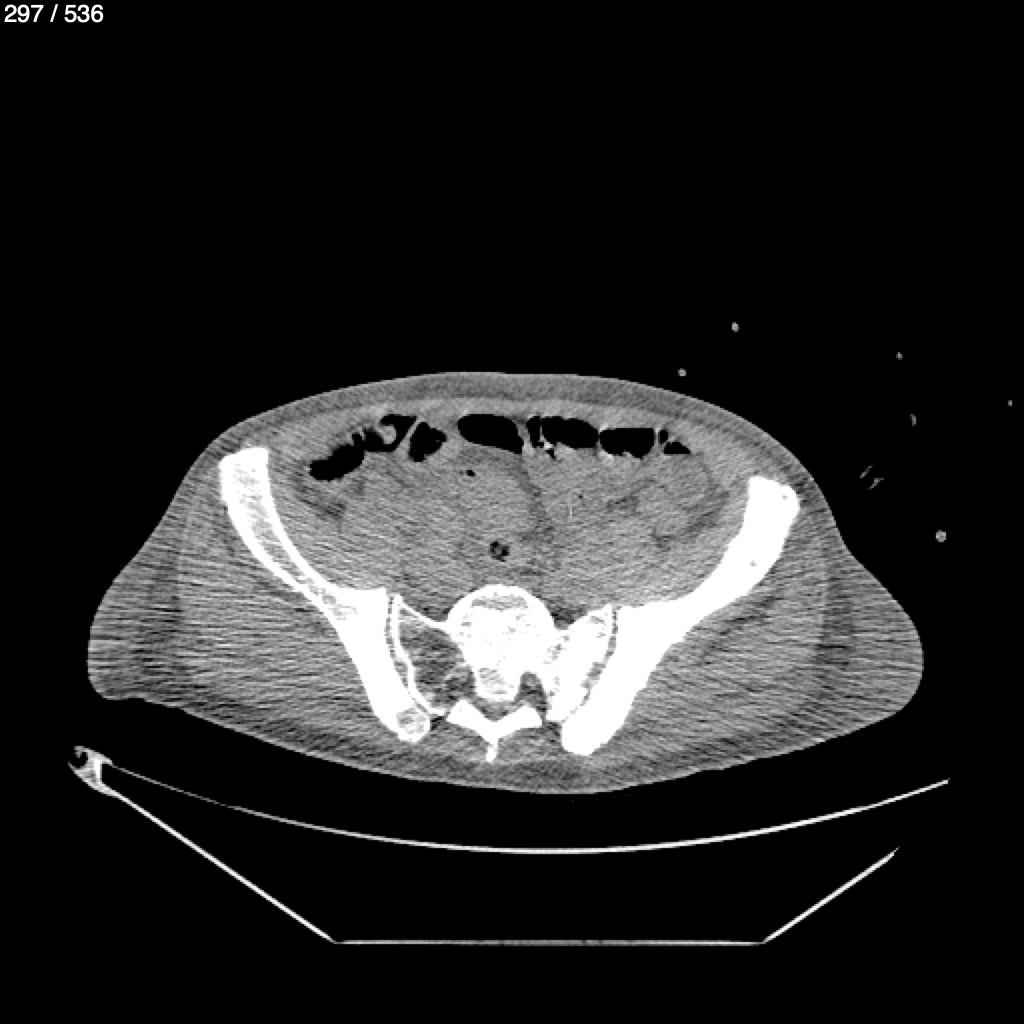

Angel Villalobos Palomeque 73 A - T.C Abdomen Simple